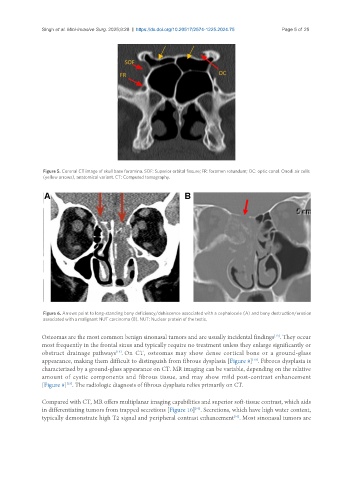

Figure 5. Coronal CT image of skull base foramina. SOF: Superior orbital fissure; FR: foramen rotundum; OC: optic canal. Onodi air cells

(yellow arrows), anatomical variant. CT: Computed tomography.

Figure 6. Arrows point to long-standing bony deficiency/dehiscence associated with a cephalocele (A) and bony destruction/erosion

associated with a malignant NUT carcinoma (B). NUT: Nuclear protein of the testis.